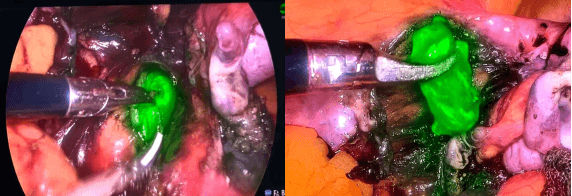

▲图为陈艳主任(右二)带领团队骨干王婷婷副主任医师(左一)、李帅副主任医师(中,背对)开展荧光显影腹腔镜下前哨淋巴结切除术,麻醉科王志龙副主任医师(右一)负责麻醉及术中生命监护。

陈艳主任团队术前充分评估,结合患者病情与身体状况,并邀请麻醉科王志龙副主任医师详细会诊评估麻醉风险后,创新性采用荧光显影导航技术,以4K荧光腹腔镜系统为核心,通过注射安全型荧光示踪剂,实时动态追踪淋巴引流路径,精准锁定并切除“前哨淋巴结”——这一技术可实现前哨淋巴结定位准确率超95%,避免传统盲扫的遗漏或误伤。